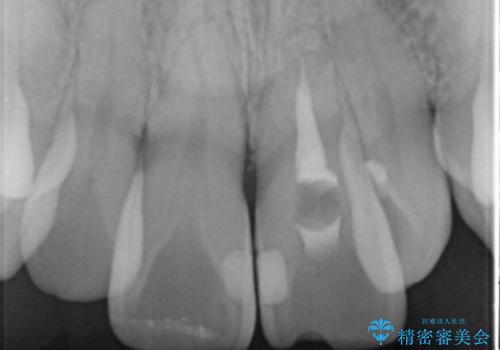

X線写真より、以前に神経の治療が為され変色をきたしている状態であることがわかりました。

根管内の感染は認められないのでセワミッククラウンの製作・装着を行い審美性を改善します。